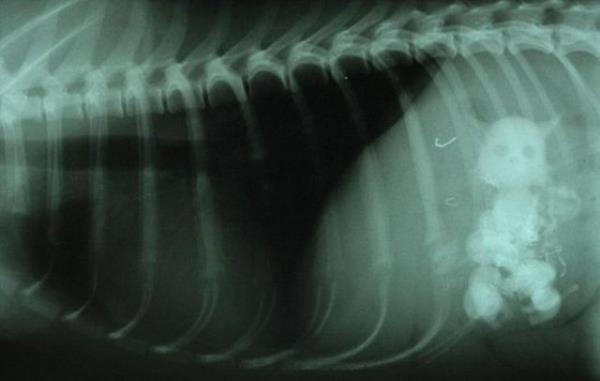

6. Snowy'nin röntgenlerinde evde bulunan en büyüğü 5 santimetre uzunluğundaki beş seramik kedi biblosunu yutmuş olduğu görüldü.

Snowy'nin röntgenlerinde evde bulunan en büyüğü 5 santimetre uzunluğundaki beş seramik kedi biblosunu yutmuş olduğu görüldü.

7. Reed, "Röntgen sonuçları için veterinerden arayıp röntgen sonuçların 'Köpeğiniz beş kedi yutmuş' dediğinde duyduklarıma inanamadım. Gerçek kediler sandım. Neyse ki iyi olduğu için mutluyuz. Bir daha olmaması için elimizden geleni yapacağız" diye konuştu.

Reed, "Röntgen sonuçları için veterinerden arayıp röntgen sonuçların 'Köpeğiniz beş kedi yutmuş' dediğinde duyduklarıma inanamadım. Gerçek kediler sandım. Neyse ki iyi olduğu için mutluyuz. Bir daha olmaması için elimizden geleni yapacağız" diye konuştu.